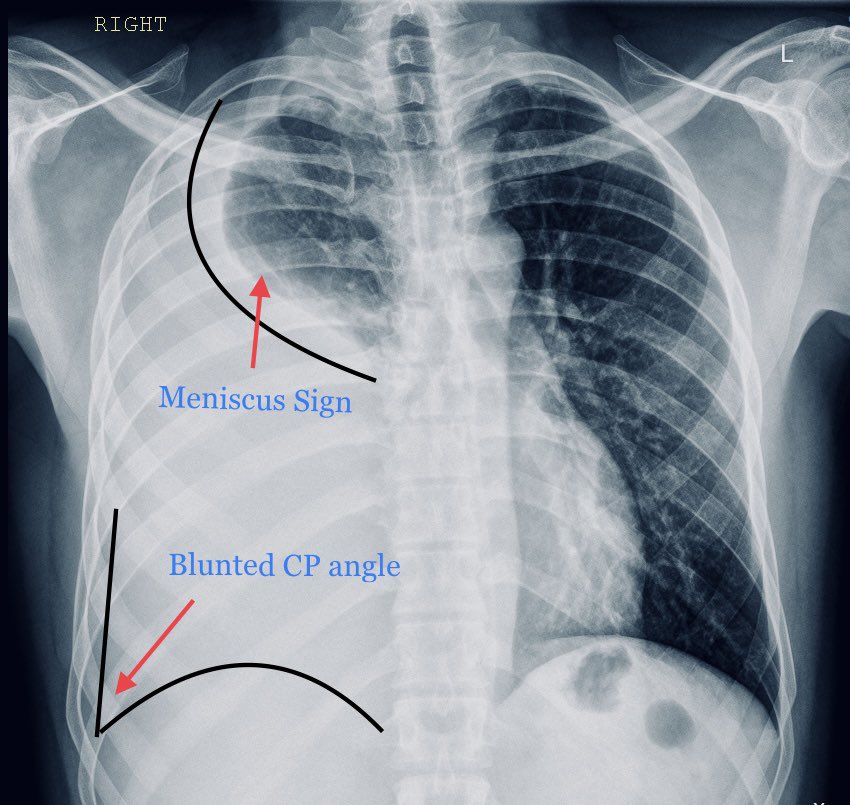

DocXus Right-sided Pleural Effusion โž” Blunted right costophrenic angle โž” Meniscus sign (concave line) at right lung base โž” indicates fluid accumulation โž” Increased density in right lower lung fields โž” suggests right-sided pleural effusion

<a href="/docxusofficial/">DocXus</a> Right-sided Pleural Effusion

โž” Blunted right costophrenic angle

โž” Meniscus sign (concave line) at right lung base โž” indicates fluid accumulation

โž” Increased density in right lower lung fields โž” suggests right-sided pleural effusion